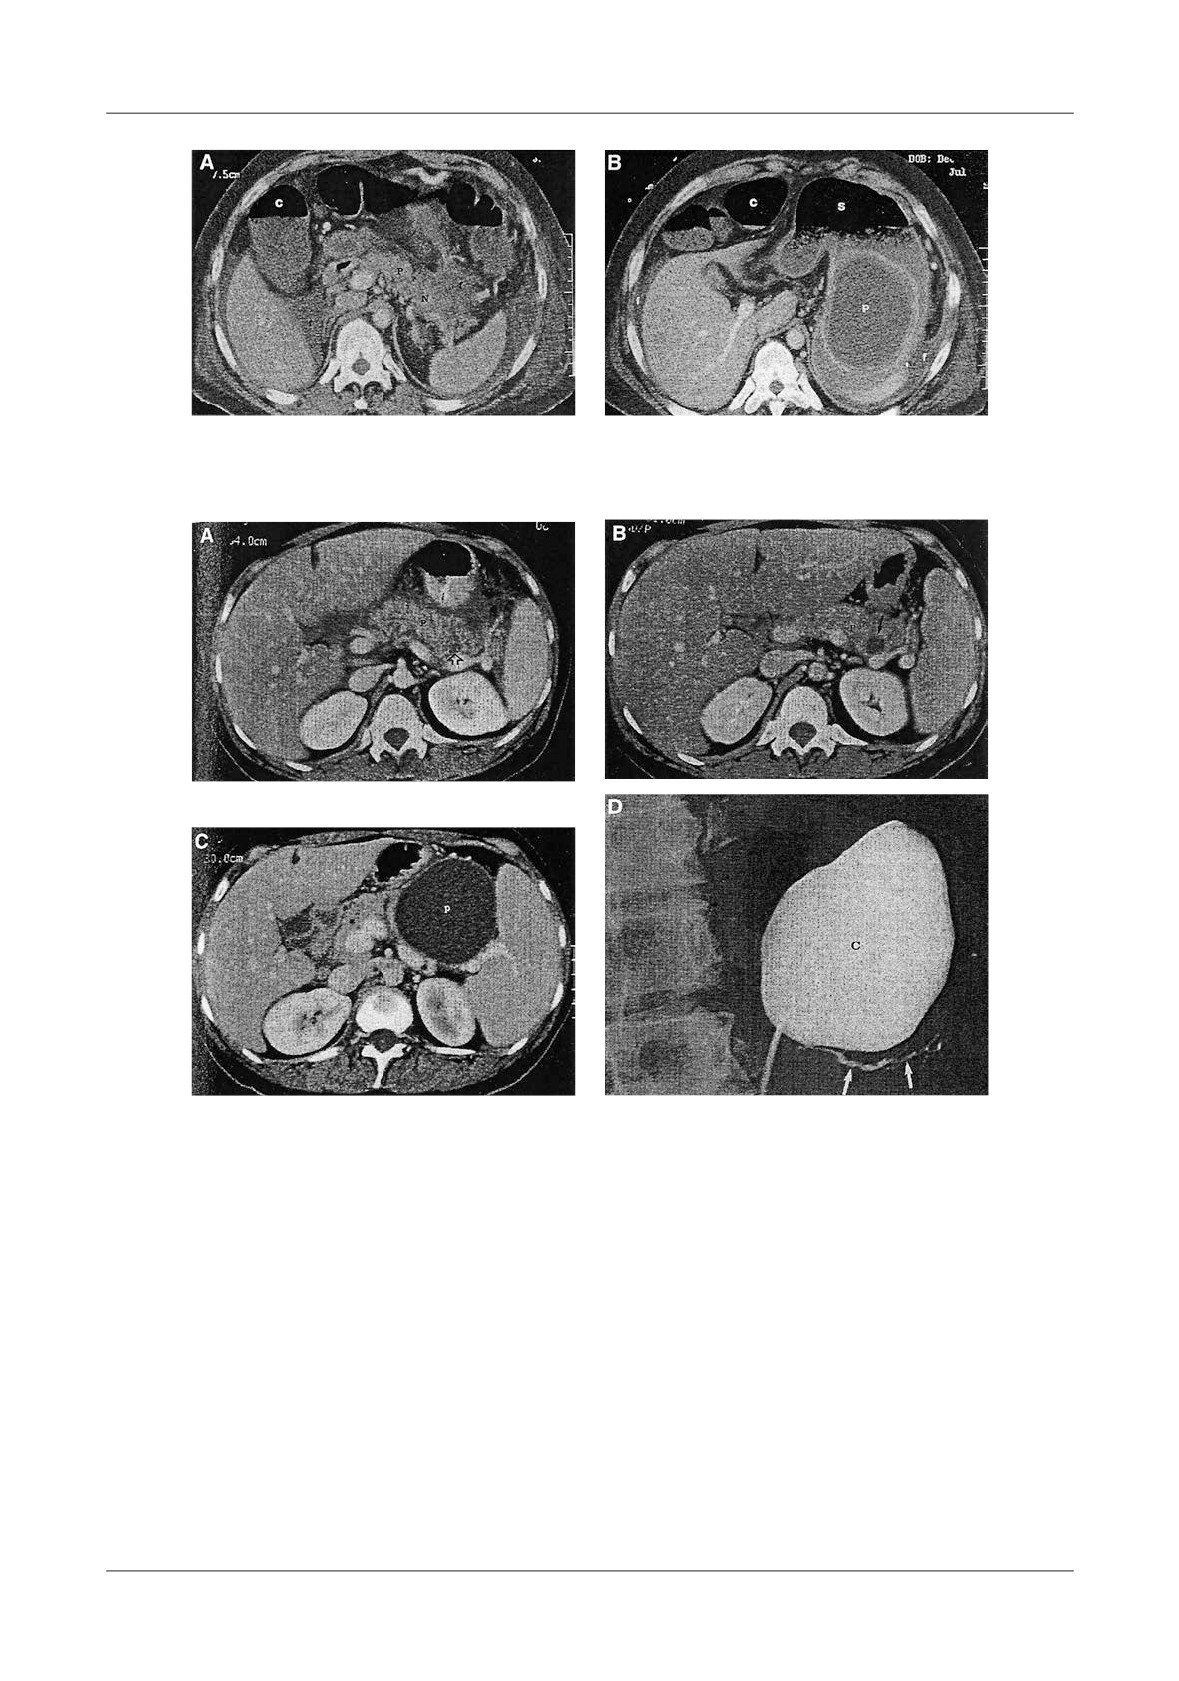

Figure 1. Pancreatic necrosis with the development of a pseudocyst, ileus and colonic in ltration in a 38

-year-old man. A-At admission the CT- shows enlarged pancreas and peripancreatic in ammation,  uid

(N=necrosis, P=pancreas, S=stomach), B-Lique ed necrosis nine days later with partially encapsulated

uid collection in the lesser sac, C-Dilated small bowel loops, with a haustral transverse colon. S=small

bowel, T=transverse colon, D-Five weeks later, fully encapsulated pseudocyst in the lower sac, with

lique ed necrosis in the neck of the pancreas (D=duodenum, N=necrosis, P=pseudocyst, S=stomach)

Figure 4. Pancreatic pseudocyst secondary to necrosis.

A - Liquefaction necrosis in the tail, B - Large pseudocyst bulging into the stomach

Figure 5. Pseudocyst communicating with  the pancreatic duct, A-With CT image of enlarged gland

and peripancreatitis, B-After discharge from hospital, 2 weeks later, CT shows a residual collection,

C-6 months later, the patient had abdominal pain, CT shows an enlarging pseudocyst,

D-Trans gastric punction with  stulography, shows communication with the Wirsung duct